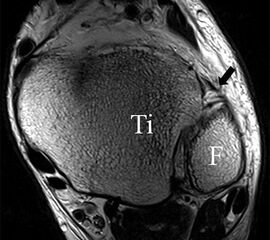

Die Kombination aus 3 Tesla Hochfeldtechnik und/oder Verwendung hochauflösender Spulen (Empfangseinheiten des Signals) erhöht die Signalausbeute. Dies erlaubt mit akzeptablen Messzeiten (3-4 Minuten pro Sequenz) im Routinebetrieb eine Darstellung mit einer Schichtdicke von 1-2 mm und einer Ortsauflösung von 0,2 x 0,2 mm in der Schichtebene in den anatomisch am besten zeichnenden 2D Turbospinechosequenzen. Der Unterschied der diagnostischen Wertigkeit zwischen einer kernspintomographischen „Standarduntersuchung“ und einer HR-MRT wird besonders in der chondralen Diagnostik sichtbar (Abb. 1 a-c). Unter Verwendung von 3D Sequenzen, die jedoch entscheidende Schwächen bei der Darstellung der Ligamente aufweisen, werden sogar Schichtdicken weit im Submillimeterbreich erreicht. Eine weitere Erörterung der Sequenz spezifischen Eigenheiten soll jedoch an dieser Stelle unterbleiben.